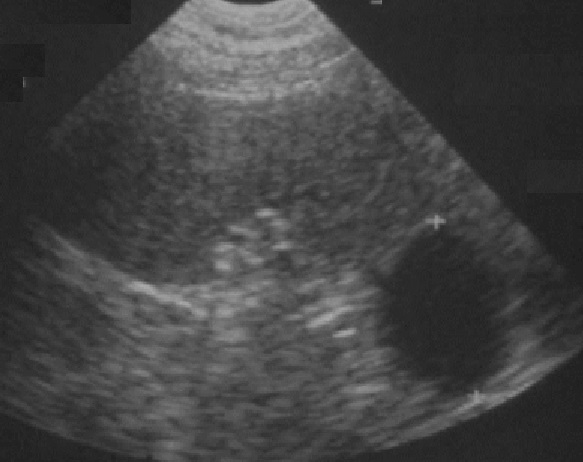

Un autre cas de kyste endothelial simple

de la rate à aspect kystique aechogène ovalaire à

bord fine , nette avec image de cône de renforcement

hyper echogene posterieure |